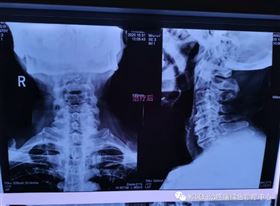

治疗前李老师颈椎X线检查影像

1个疗程治疗后颈椎X线检查对比